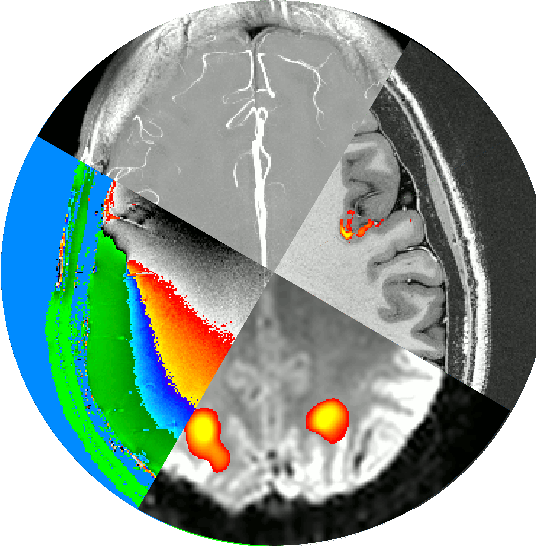

In this this Hackathon project, we aim to develop a purely uni-directional (safe) data streaming “hack” to transfer MRI data directly to the cloud by means dynamic QR codes.

In the early days of the Internet, modems (modulator-demodulator) were used to (i) convert digital information into audio streams, (ii) transfer them across telephone lines, and (iii) convert them back into the digital domain. Here, we aim to do the same thing with pixel data of MRI scans. However, instead of audio signal we will use machine-readable visual information: QR codes.